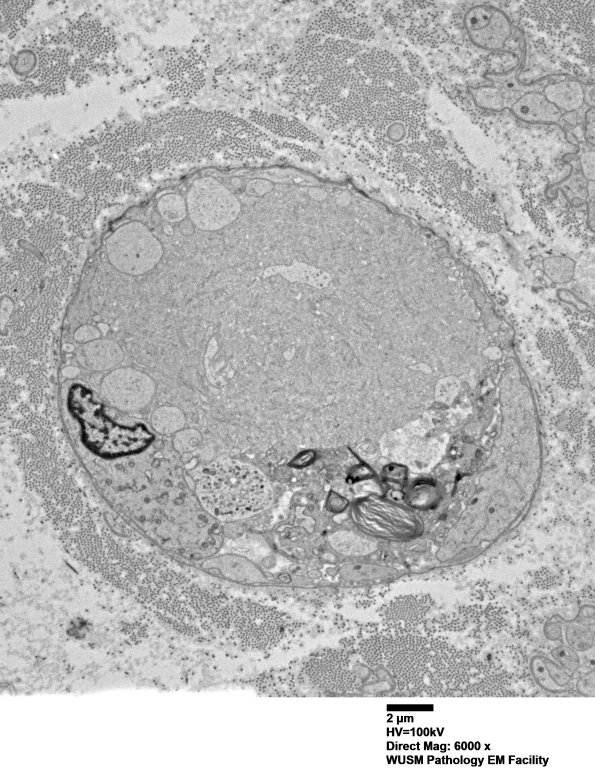

This appears to be a spheroid surrounded by Schwann cell processes and residual myelin debris. We have questioned if the vesicular elements could represent vesicular myelin change and not an axonal element. There is no definitive Schwannian element found within the spheroids and many were available for examination. (electron micrograph)